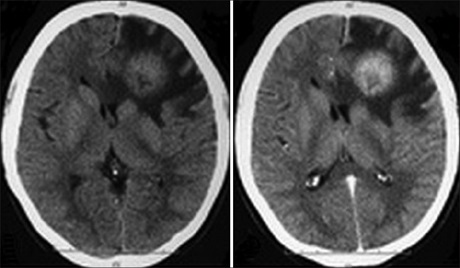

Incidental Findings on Computed Tomographic scans in Patients with Head Trauma in Ilorin, Nigeria

Dr. Oyinloye Olalekan Ibukun, Yusuf Ayodeji Salman, Jimoh Kamaldeen Olayori (Author)

75-79